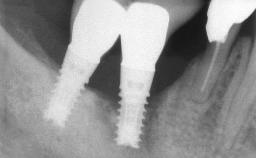

Biological complications caused by undetected cement residue have been receiving much attention. Excess cement might be responsible not only for rapidly developing of peri-implantitis, but also for delayed or chronic manifestations of the disease many years after cementation (Wilson 2009; Linkevicius and coworkers 2013). Invitro and clinical studies have shown that it is very difficult or even impossible to completely clean up excess cement at subgingival margins, so popular in cemented restorations (Agar and coworkers 1997; Linkevicius and coworkers 2011, 2012). Possible outcomes of biological complications due to excess cement range from temporary inflammation of the peri-implant soft tissues without any serious esthetic and functional consequences all the way to implant loss. This report describes a case of peri-implantitis caused by residual cement; as well as the management and quite unusual resolution of the complication. The patient presented in 2009 with a draining sinus tract, tenderness on chewing, and tissue contact above the implant-supported restoration. The implant had been restored approximately three years before.